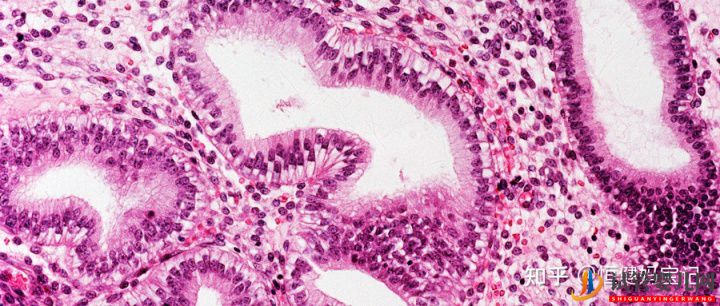

做試管嬰兒時(shí),為保證試管嬰兒妊娠概率,一般醫(yī)生會根據(jù)患者身體情況,移植1-2枚胚胎。如果兩個(gè)試管嬰兒網(wǎng):胚胎到了女性子宮內(nèi)同時(shí)存活,就是雙胞胎,所以說試管嬰兒懷雙胞胎的幾率要大于自然受孕。